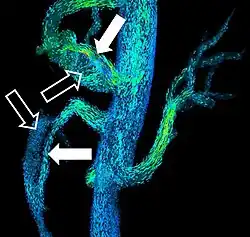

Angiograma de MR em doença cardíaca congênita.

A RM cardíaca é complementar a outras técnicas de imagem, como ecocardiografia, TC cardíaca e medicina nuclear. As suas aplicações incluem avaliação da isquemia miocárdica e viabilidade, cardiomiopatias, miocardite, sobrecarga de ferro, doenças vasculares e cardiopatia congênita.[46]

Angiografia por ressonância magnética

A angiografia por ressonância magnética (MRA) gera imagens das artérias para avaliá-las para estenose (estreitamento anormal) ou aneurismas (dilatação da parede vascular, em risco de ruptura). O MRA é frequentemente usado para avaliar as artérias do pescoço e do cérebro, a aorta torácica e abdominal, as artérias renais e as pernas (chamado de "escorrer"). Uma variedade de técnicas podem ser usadas para gerar as imagens, como a administração de um agente de contraste paramagnético (gadolínio) ou usando uma técnica conhecida como "aprimoramento relacionado ao fluxo" (por exemplo, sequências de tempo de voo 2D e 3D), onde a maior parte do sinal em uma imagem é devido ao sangue que recentemente se mudou para esse plano. As técnicas que envolvem acumulação de fase (conhecida como angiografia por contraste de fase) também podem ser usadas para gerar mapas de velocidade de fluxo com facilidade e precisão. A venografia por ressonância magnética (MRV) é um procedimento similar que é usado para imagens de veias. Neste método, o tecido agora está excitado inferiormente, enquanto o sinal é recolhido no plano imediatamente superior ao plano de excitação - criando assim o sangue venoso que recentemente se moveu do plano excitado.[52]